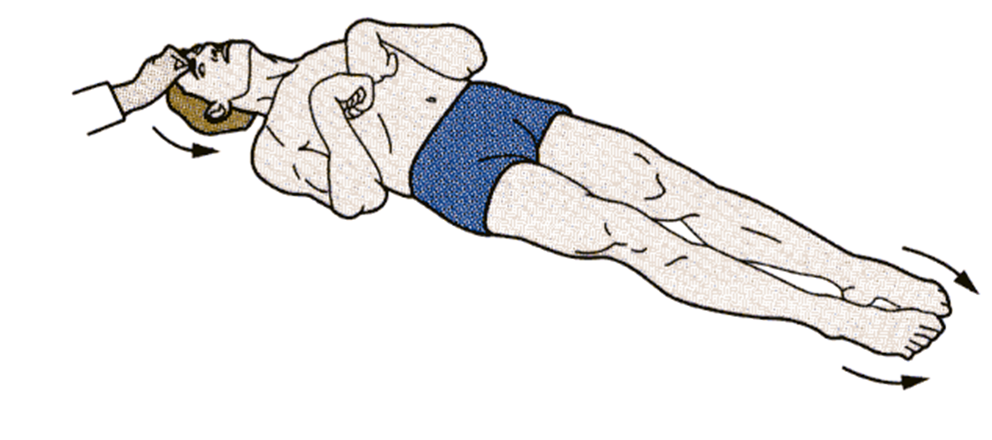

what posturing? which tracks are impaired

decorticate posturing. rubrospinal intact